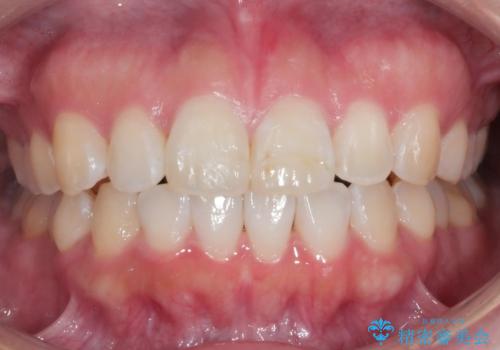

[マウスピース矯正] がたがたの歯並びをきれいにしたい

![[マウスピース矯正] がたがたの歯並びをきれいにしたいの症例 治療前](https://seimitsushinbi.jp/wp/wp-content/uploads/2025/06/0d238550c8a0fddc4de7b2c337c6c786-500x350.jpg?v=1750323380)

![[マウスピース矯正] がたがたの歯並びをきれいにしたいの症例 治療後](https://seimitsushinbi.jp/wp/wp-content/uploads/2025/06/IMG_0002-2-500x350.jpg?v=1750323305)